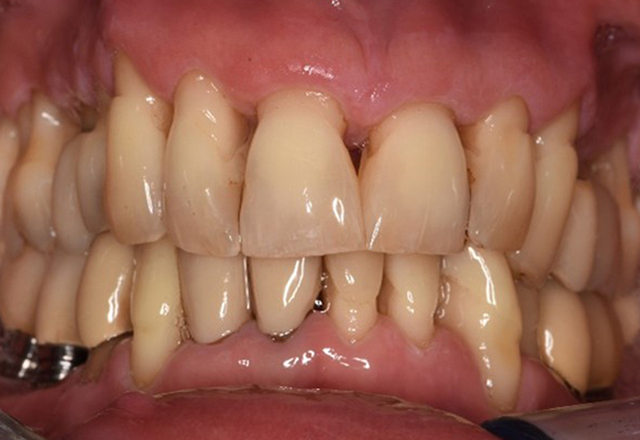

Case presentation: Complex Dental Prosthesis Management

The direct relationship between intraoral and general health, as well as the bidirectional influence that they may have on one another, is well-known (1,2). It is absolutely essential to consider both factors when planning preventive intraoral measures and treatment in the dental practice. The primary objective is the maintenance of patient health and quality of life from both dental and medical perspectives. more